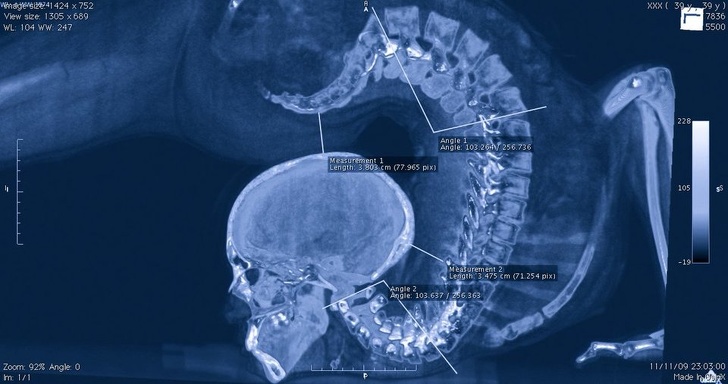

Хребет акробата на рентгені